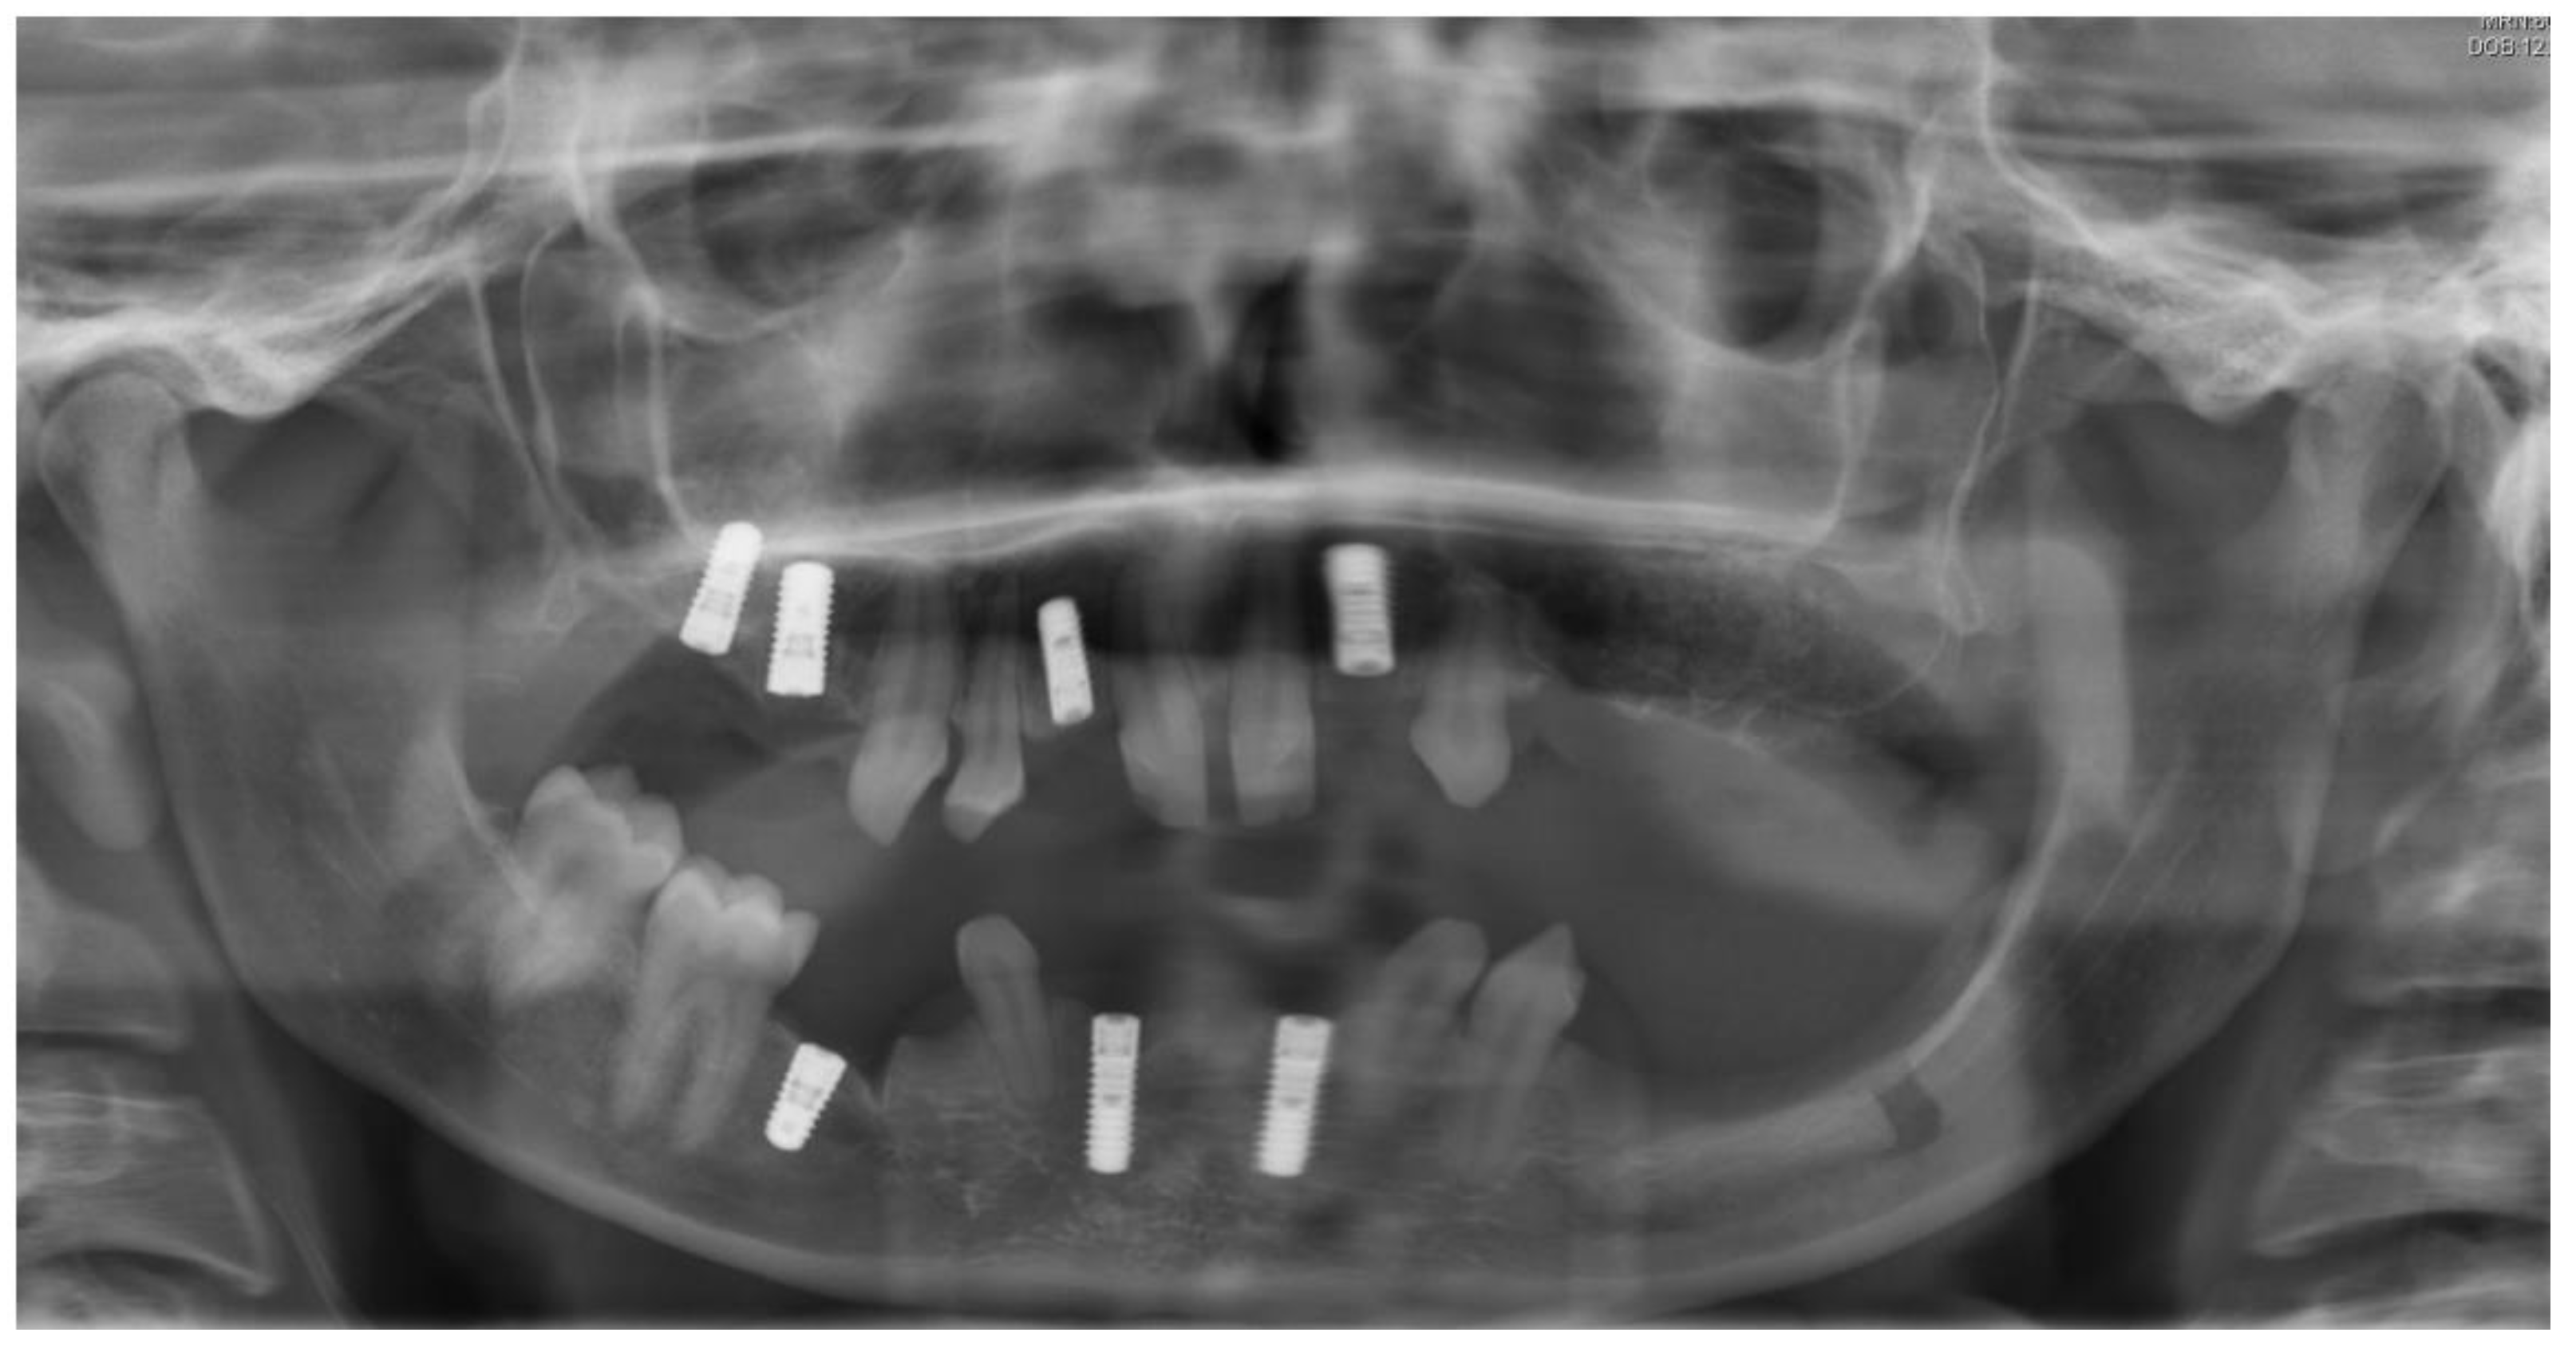

Figure 2.

Panoramic radiography after bone graft, nerve lateralization, and placement of dental implants in edentulous sites with adequate bone volume.

The first surgical procedure included nerve lateralization at the left lower jaw, sinus lift, and placement of dental implants in edentulous sites with adequate bone volume. In order to reduce the risk of nerve injury related to the exacerbated bone atrophy at left lower jaw, the placement of dental implants at the left site was planned digitally (Figure 2).

The placement of two titanium dental implants (Bone Level 4.1 × 8 mm, Straumann) at premolar and molar sites (35, 36) was planned. Surgical procedures were conducted under local anesthesia following a healing period of three months prior to implant exposure and prosthetic rehabilitation. Figure 5 shows the final prosthodontic rehabilitation at one year follow-up. Clinical outcomes showed osseointegration of dental implants and health of peri-implant tissues.

Figure 5.

Left: final orthopantomogram showing the dental implants. Right: intra-oral situation after final rehabilitation with dental-supported and implant-supported prosthesis [12].